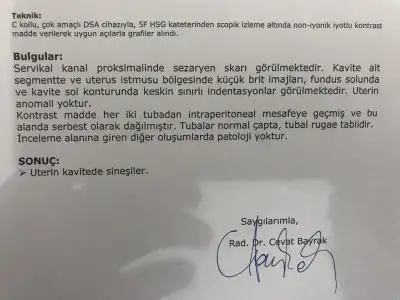

Ben hsg görüntümü ekliyorum.uludag uni tıp fakultesinde rahim filmi çektiren görüntüsünü ekleyebılır mı ? Benim rahim filmim mi sıkıntılı çekim sırasında sorun mu oldu acaba değişik geldi merak ediyorum

Özelde çektirdiğim hiç bu şekilde değildi. Umarım hatalı çekim veya sorun oluşturabılecek birşey yoktur. 4 gündür kahverengi akıntım devam ediyor.

Akıntın geçti mi ben de ha geçti ha bitti derken hala devam ediyo pazartesi çekilmiştim hala akıntı geliyo yaniBen hsg görüntümü ekliyorum.

Özelde çektirdiğim hiç bu şekilde değildi. Umarım hatalı çekim veya sorun oluşturabılecek birşey yoktur. 4 gündür kahverengi akıntım devam ediyor.